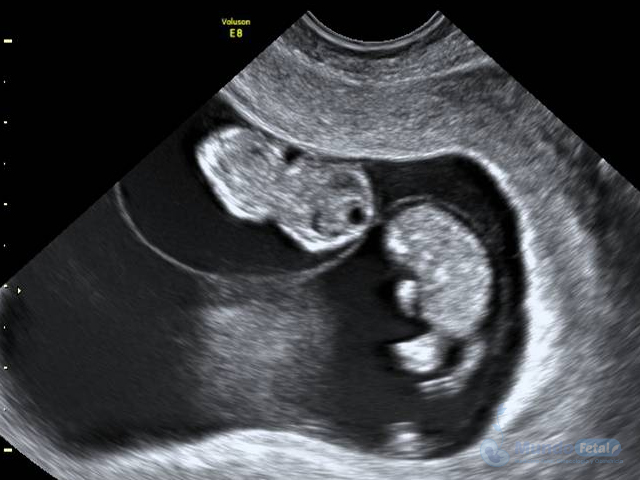

Es esencial detectarlo desde el primer trimestre (especialmente 11-13.6 semanas de gestación) con la intención de conocer el número de bebes, cuántas placentas y bolsas amnióticas, ya que el seguimiento de estos es distinto, esto por los riesgos que conllevan de presentar alguna alteración propia de estos embarazos, indicativos de una vigilancia estrecha y estudios complementarios, durante toda la gestación.

• Valorar el mejor momento del nacimiento.